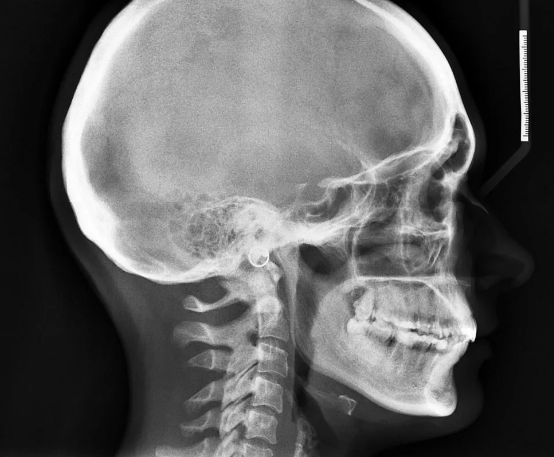

Чисто для интереса сравните с современными снимками.